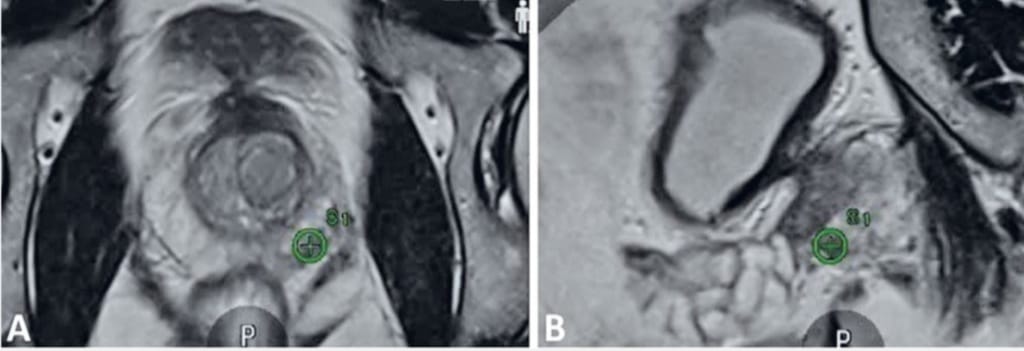

Az új technika a multiparametrikus MRI-vizsgálat képeit ötvözi a valós idejű, transzrektális ultrahangvezetéssel. A speciális szoftver a két képanyagot egy háromdimenziós, rendkívül részletes térképpé alakítja, így az orvosok pontosan tudják meghatározni, mely prosztataterületekről szükséges mintát venni. Ez jelentős előrelépés a korábbi, úgynevezett „vakon” végzett biopsziákhoz képest, hiszen a célzott szövettani mintavétel lényegesen növeli a diagnózis megbízhatóságát.

A módszer fontos előnye, hogy a PIRADS-pontszám alapján korábban gyanúsnak ítélt elváltozásokat célzottan lehet vizsgálni. Ennek köszönhetően az orvosi csapat sokkal pontosabban tudja meghatározni a további kezelési irányt – legyen szó aktív megfigyelésről, fókuszált beavatkozásról vagy akár radikális terápiáról. A technológia egyszerre biztosít nagy precizitást, biztonságot és kényelmet, ezzel erősítve a korszerű képalkotó diagnosztika szerepét a korai felismerésben.